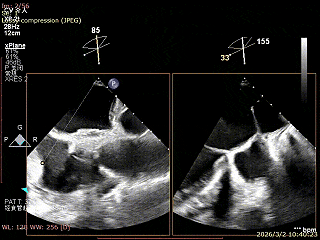

双孔组织桥稳定

3D enface反流充分降低

术后平均跨瓣压差2mmHg